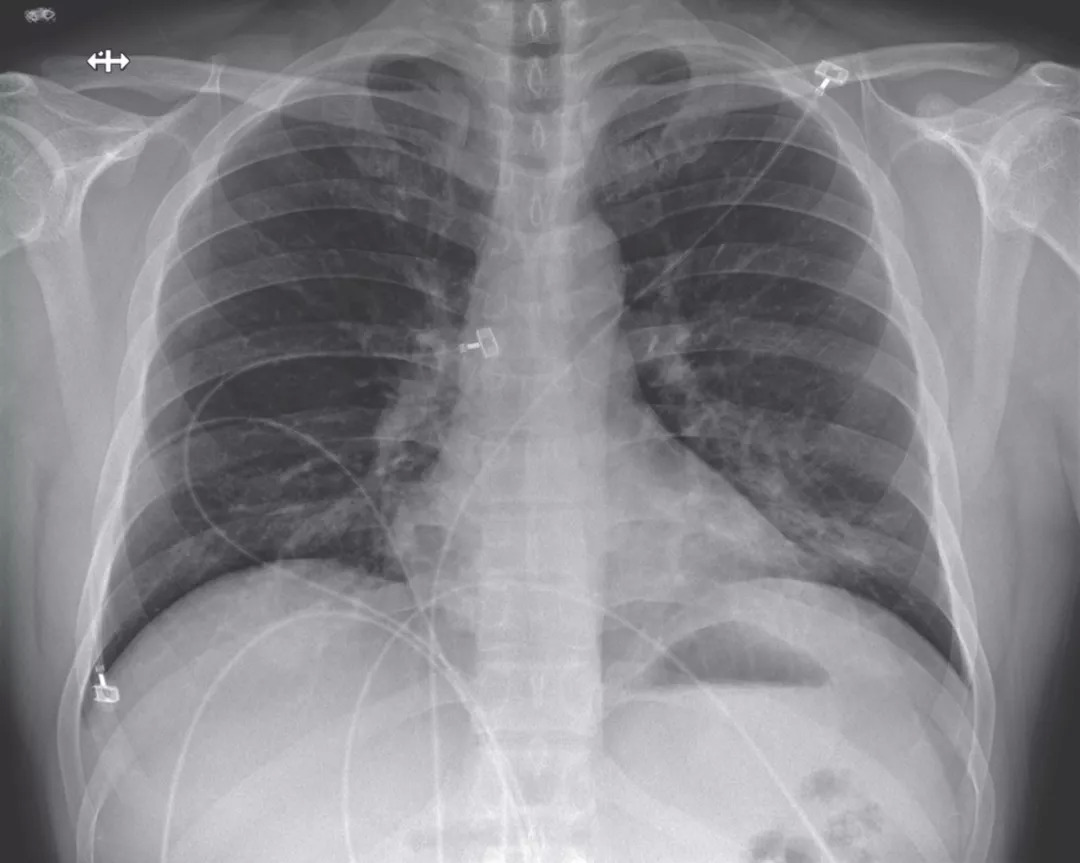

图一:后胸部和外侧胸部X光片